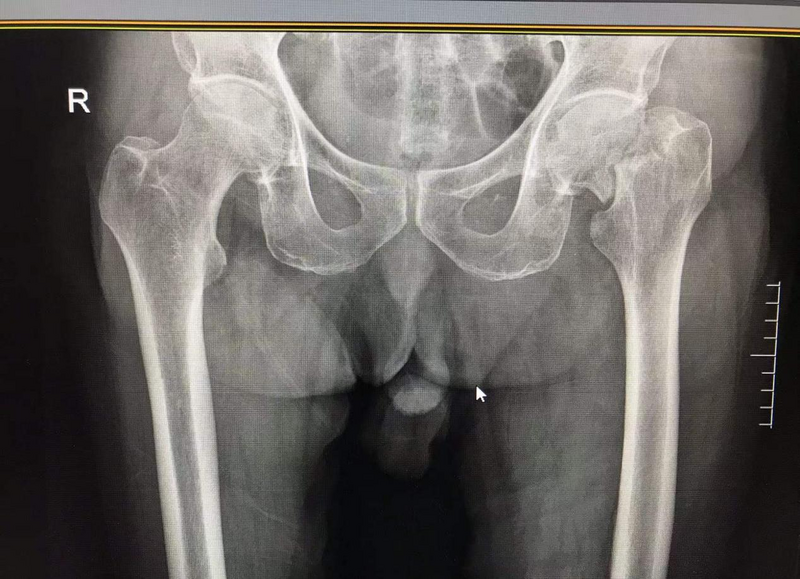

術(shù)前患者股骨頸骨折